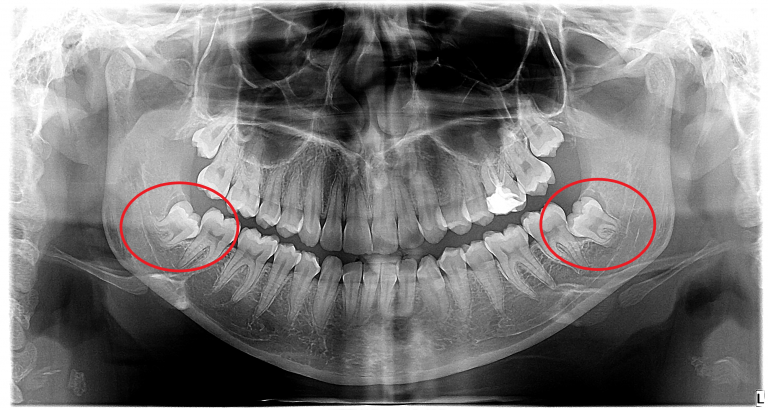

Impaktirani zubi predstavljaju potpuno ili delimično neiznikle zube. Impakcija zuba nastaje iz različitih uzroka (genetske predispozicije, ortodontskih nepravilnosti, nesrazmerna veličina zuba i vilica, nepravilan položaj klice zuba prilikom razvoja), a najčešće impaktirani zubi su umnjaci ili treći molari koji se poslednji pojavljaju u ustima između 18. i 25. godine živote.

Impaktirani umnjaci mogu izazvati bolove i nelagodnosti prilikom pokušaja zuba da nikne, ugroziti susedne zube i njihove korene svojim položajem, poremetiti zubni niz, a neretko i biti uzrok formiranja cista u koštanom tkivu. Kod delimično impaktiranih umnjaka česta je pojava karijesa i perikoronitisa (infekcije mekog tkiva oko umnjaka).

Dijagnoza impaktiranog ili delimično impaktiranog zuba se uspostavlja kliničkim pregledom i rendgenskim snimkom.

Vađenje impaktiranih zuba obavlja se hirurškim putem u lokalnoj anesteziji. Nakon operacije neophodno je pridržavati se uputstva koja dobijate od stomatologa, kako bi oporavak bio lagodniji, a konci se uklanjaju sedam do deset dana od operacije.